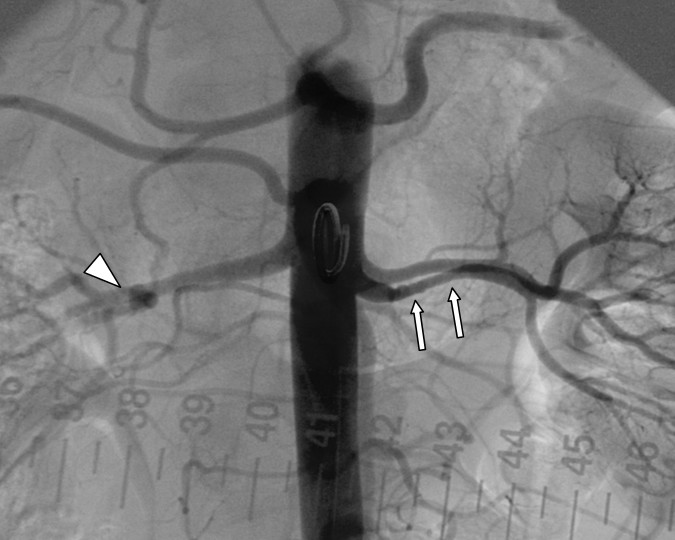

Die oben gezeigte Stenose nach Aufdehnung (PTA) Die oben gezeigte Stenose nach Aufdehnung (PTA) © wikipedia/Zeina AR, Vladimir W, Barmeir E. (CC2.0)